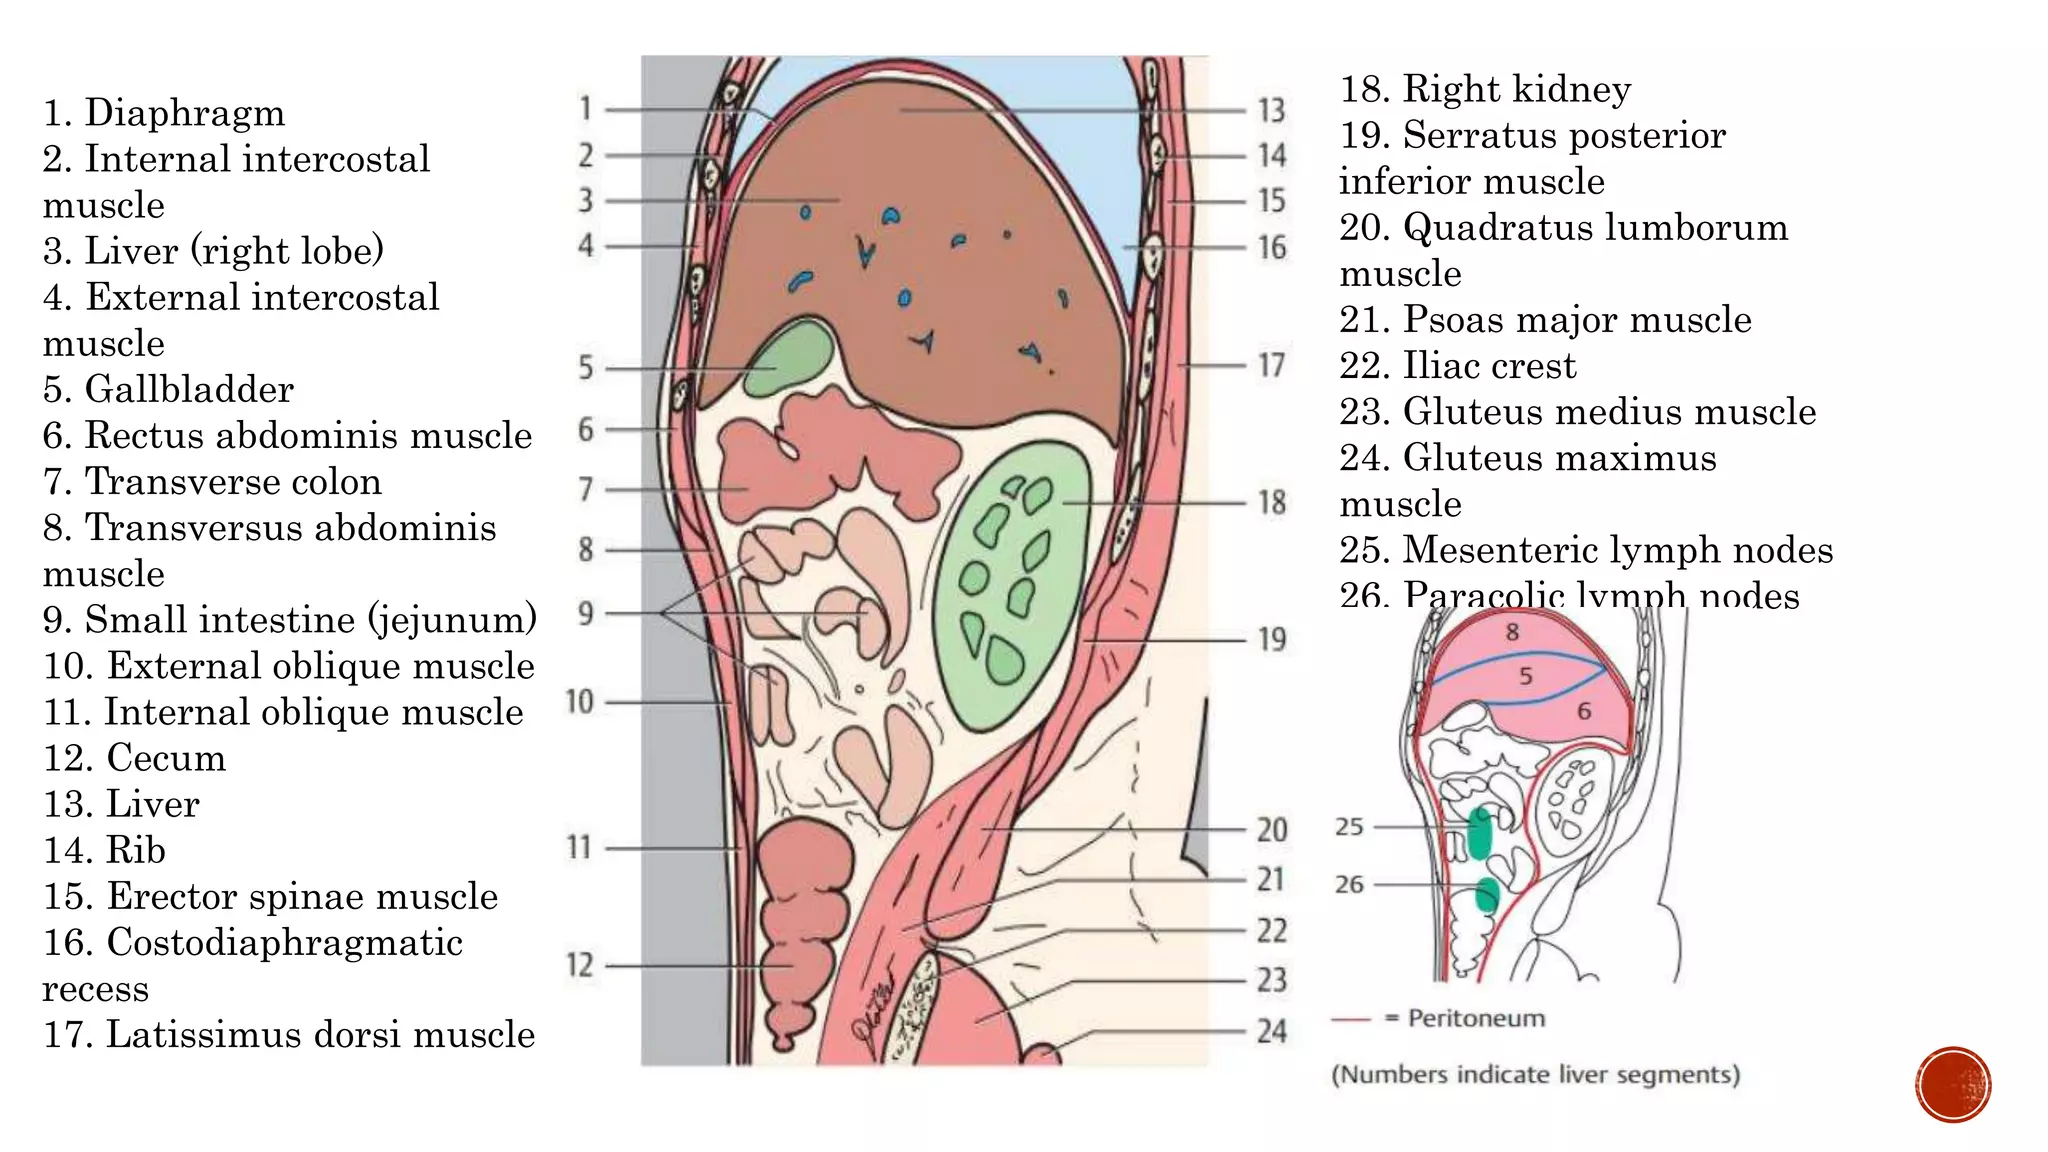

The document describes the anatomy of the abdomen and pelvis region of the human body. It lists over 40 structures and their locations, including major organs like the liver, kidneys, intestines, blood vessels and muscles of the abdominal wall and pelvis. The structures are grouped into sections focusing on different anatomical areas like the abdomen, retroperitoneum, pelvis and gluteal region.